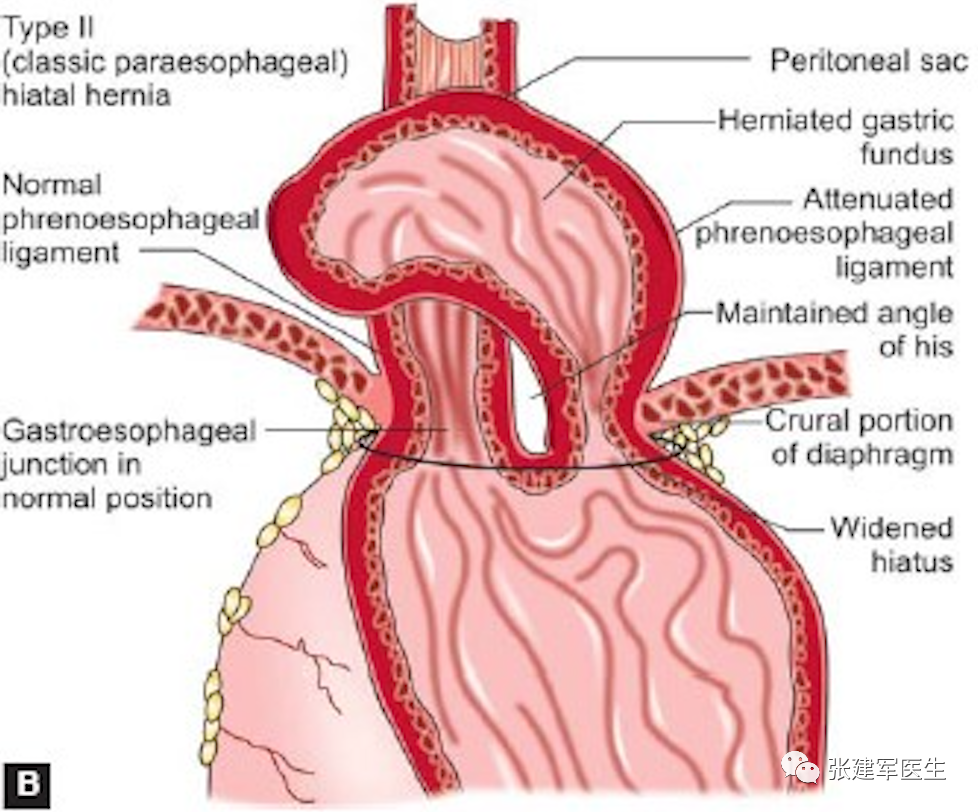

食管裂孔疝主要有两种类型:滑动性食管裂孔疝和食管旁食管裂孔疝。大多数为滑动型食管裂孔疝,即1 型。其他三种类型均为食管旁疝。

II型(食管旁疝或滚动性食管裂孔疝):胃食管结合部在膈肌下正常解剖位置,胃底或胃体通过胃食管裂孔疝入胸腔,胃底在食管胃结合部上方。